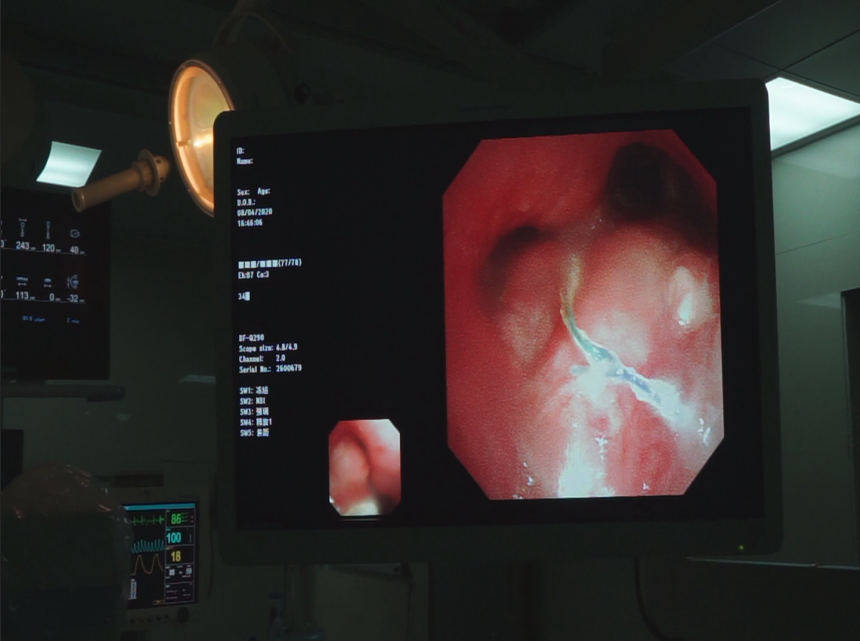

此时张先生生命危在旦夕,时间急迫,在与家属多次沟通并取得同意后,牛院长团队决定为他实施纤维支气管下左侧支气管消融术+DSA引导下左侧支气管支架置入术。

2020年4月8日,牛院长团队通过DSA+CT技术不仅快速准确找到狭窄的支气管,还更为清楚地看到肿瘤及其他周围组织的关系。在气管镜下,牛院长熟练进行着进导丝、送置入器、释放支架等等步骤;随后在微波射频消融设备下,将穿刺针刺入纵膈上的肿瘤部位,利用射频发热原理使肿瘤部位坏死。历时一个半小时手术顺利结束。